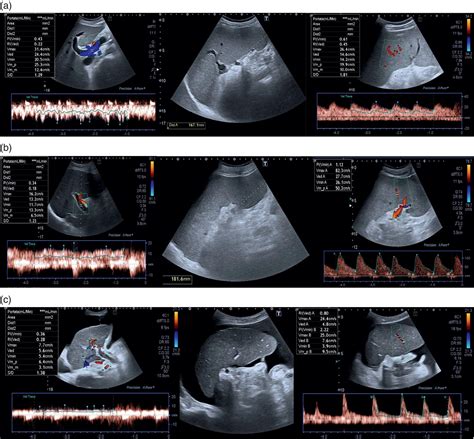

A liver ultrasound, also known as a hepatic sonogram, functions by emitting sound waves that bounce off internal structures. The transducer, a handheld device, captures these echoes and transforms them into visual representations on a monitor. Because the liver has a distinct texture, or "echogenicity," radiologists can quickly differentiate between healthy tissue and potential pathology.

When clinicians review liver ultrasound images, they look for changes in size, shape, and internal patterns. The consistency of the liver’s surface and the presence of any masses are critical markers for diagnosing conditions ranging from simple cysts to more complex oncological issues.

Advanced imaging techniques, such as contrast-enhanced ultrasound or subsequent MRI/CT scans, may be requested if the initial findings are inconclusive. These follow-up tests provide higher resolution and dynamic blood flow data, allowing medical professionals to differentiate between benign and malignant liver processes with greater precision.

For patients with chronic liver conditions, such as Hepatitis B or C, serial imaging is essential. By comparing current liver ultrasound images with previous scans, doctors can monitor the progression of disease or the success of ongoing treatments. This longitudinal approach is vital for the early detection of hepatocellular carcinoma, which is significantly easier to treat when found during the early stages of development.